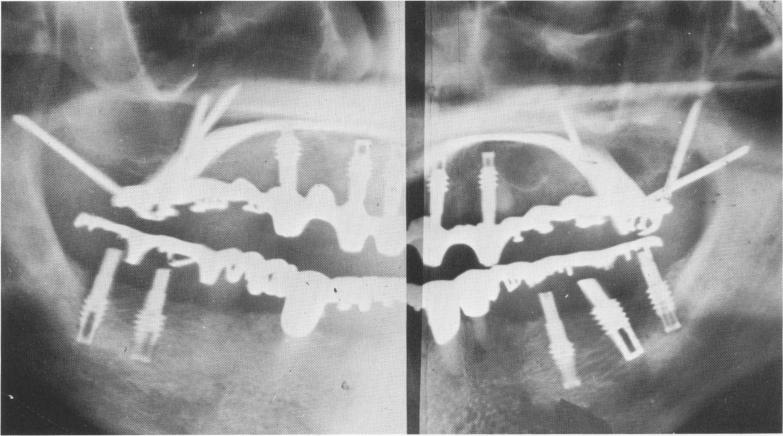

Fig. 10-252. A postoperative Panorex reveals the five vent-plants, two posterior triplants, scalloped template, and posterior palatal connecting bar. Notice also that this patient had lower vent-plants that he had been using successfully for 3 years previous to the upper re-construction. Since the lower posterior pontics were constructed mostly of acrylic, only the gold occlusal surfaces are seen.

To start implant insertion, round or spear-point burs were drilled through the hollow tubes into bone. Various sized helical burs replaced the initial burs

1 Ventplant, triplants, scalloped template & palatal connecting bar